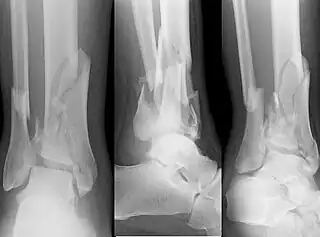

En medicina, se denomina fractura de pilón tibial a un tipo de fractura de tibia que se caracteriza por afectar tanto a la epifisis distal como a la metáfisis del hueso, comprometiendo la articulación del tobillo. Es un tipo de fractura de gran complejidad y de pronóstico grave, existiendo dificultades para alcanzar la curación completa, pudiendo quedar secuelas permanentes.[1][2]

![]() Fractura de pilón tibial asociada a fractura de peroné | ||